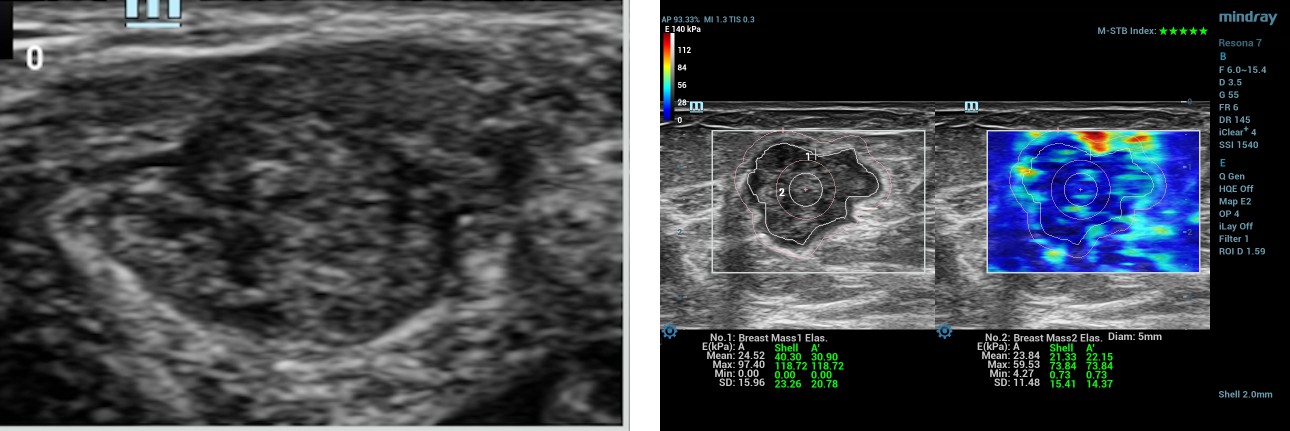

57-year-old female, patient A presented with a left breast lump of 6 months duration. There was a lump measuring 19x15mm in size at the 2 O’clock position of the left breast. B-mode ultrasound categorized this lesion as BIRADS 5. Before performing the biopsy, the patient underwent shear wave elastography (SWE) using L14-3WU (bandwidth frequency = 3.8-15.4 MHz, FOV-50.8mm) linear array transducer of Resona 7 diagnostic ultrasound system by Mindray Medical International, Shenzhen, China.

swe-prior-breast-mass-fig1-pc

Figure 1- B Mode Ultrasonography and SWE measurements in patient A

The Maximum and mean values in the selected ROI manually along the edge of the lesion are 97.4 kPa and 24.5 kPa. The maximum value in the 2mm shell around the lesion is 118.7 kPa. The maximum and mean values in the lesion + shell are 118.7 kPa and 30.9kPa. Maximum and minimum values in the center of the lesion with a circular ROI measuring 5mm in diameter are 59.5kPa and 23.8kPa.